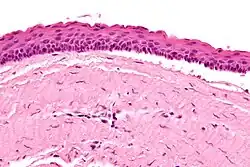

Micrograph of an odontogenic keratocyst. H&E stain.

Odontogenic keratocysts have a diagnostic histological appearance. Under the microscope, OKCs vaguely resemble keratinized squamous epithelium;[15] however, they lack rete ridges and often have an artifactual separation from their basement membrane.[2]

The fibrous wall of the cyst is usually thin and uninflamed. The epithelial lining is thin with even thickness and parakeratinised with columnar cells in the basal layer which have focal reverse polarisation (nuclei are on the opposite pole of the cell).[13] The basal cells are an indication of the odontogenic origin as they resemble pre-ameloblasts. The epithelium can separate from the wall, resulting in islands of epithelium. These can go on to form 'satellite' or 'daughter' cysts, leading to an overall multilocular cyst.[10] Presence of daughter cysts is particularly seen in those with NBCCS.[13] Inflamed cysts show hyperplastic epithelium which is no longer characteristic of OKCs and can have resemblance to radicular cysts instead. Due to areas of focal inflammation, a larger biopsy is required for correct diagnosis of odontogenic keratocysts.[10]